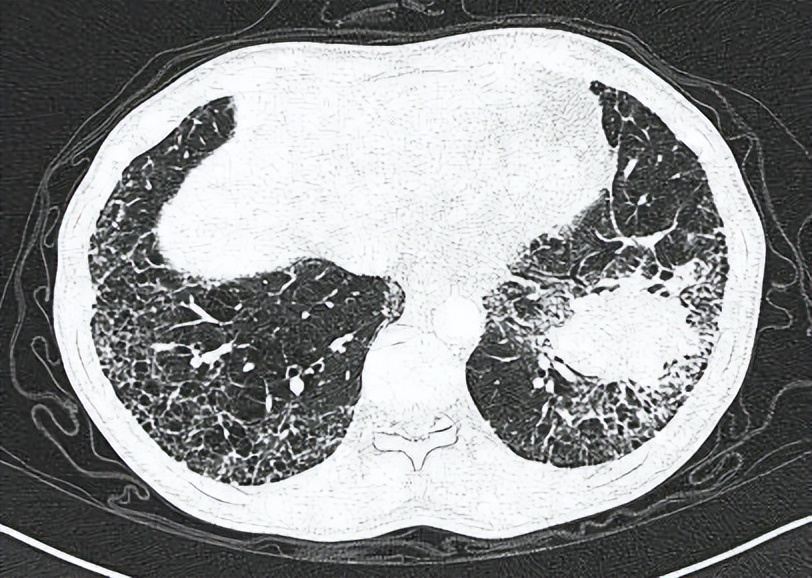

蜂窝状网格纤维化

长期以来根据病程将HP分为急性、亚急性和慢性HP,但按照病程分类难以客观反映疾病行为和预后,肺纤维化则是决定HP预后的关键因素。2020年美国胸科协会(ATS)/日本呼吸协会(JRS)/拉丁美洲胸科协会(ALAT)共同发布了《2020版成人过敏性肺炎诊断指南》,根据高分辨率CT(HRCT)和(或)组织病理学是否存在肺纤维化,将HP患者分为非纤维化性HP(单纯炎性病变)和纤维化性HP(炎性病变合并纤维化或单纯纤维化)。纤维化性HP在HRCT上的典型表现为同时存在肺纤维化和小气道病变,主要分布于中上肺野,下肺野相对正常。肺纤维化的HRCT特征包括不规则线状影或粗网格影伴有肺组织扭曲,可有牵拉性支气管扩张和蜂窝肺。小气道病变则包括小叶中央型小结节和(或)磨玻璃影、马赛克衰减、三种密度征(既往称肉皮冻征)和(或)空气潴留征(通常位于小叶分布区)。借鉴IPF的影像学诊断模式,将纤维化性HP的HRCT诊断分为典型HP、符合HP和不确定HP。具备在特定区域内HRCT肺纤维化和一项小气道病变特征,诊断为典型纤维化性HP。肺活检在明确诊断HP中发挥了至关重要的作用,对于非纤维化性HP的患者,建议选择经支气管肺活检,纤维化性 HP的患者则建议行经支气管冷冻活检,仅当所有其他诊断方法无法明确诊断时进行手术肺活检。

随着CT用于肺癌筛查和其他疾病的诊断的增多,ILA的检出逐渐增多。CT上的ILA被定义为影响超过5%的任何肺区的非重力依赖性变化,包括非重力依赖性磨玻璃或网状影、弥漫性小叶结节、囊状改变、蜂窝和牵拉性支气管扩张,分布类型包括非胸膜下、胸膜下非纤维化和胸膜下纤维化。大型队列研究中ILA发生率约为6%~10%,老年人、吸烟者和携带MUC5B启动子多态性者,ILA更为普遍[19, 20]。ILA不是独立的疾病实体,可能代表了不同类型ILD的亚临床阶段。ILA可能会发展为不同类型的ILD,20%~40%的ILA病情会在2~5年内进展,而且ILA进展与肺功能下降和死亡风险增加有关。ILA的影像类型或特征可能有助于预测疾病进展和死亡。胸膜下纤维化型的ILA进展风险最大、死亡风险高,典型UIP型和可能UIP型的患者死亡风险明显高于不确定UIP型。部分ILA患者肺组织病理学上可出现纤维化特征,包括胸膜下间质纤维化、成纤维细胞灶,蜂窝和(或)UIP。